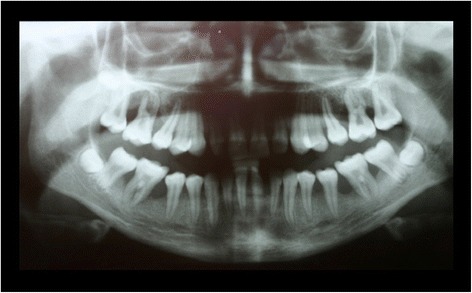

When she was 13 years old, the patient presented again for periodontal evaluation. At the time, the patient was receiving a systemic immunosuppressive therapy with mycophenolat-mophetil for the management of a severe pneumonia and hematocolpos. In addition, she was receiving longterm antibiotic therapy with ciprofloxacin and pyrazinomid for a pulmonary infection with multiresistant tuberculosis bacteria. The periodontal evaluation revealed signs of generalized severe periodontitis with gingival hyperplasia, ulceration and fibrinous pseudomembranes. The panoramic radiograph showed generalized horizontal bone loss of 10% to 30% at the upper and lower anterior teeth and vertical alveolar bone loss at all first molars (Figure 2). Four quadrant supra- and subgingival debridement was performed. The patient did not return for supportive periodontal therapy.

Figure 2.

Panoramic radiograph at the age of 13 years: no periodontal therapy was rendered since the age of 9.